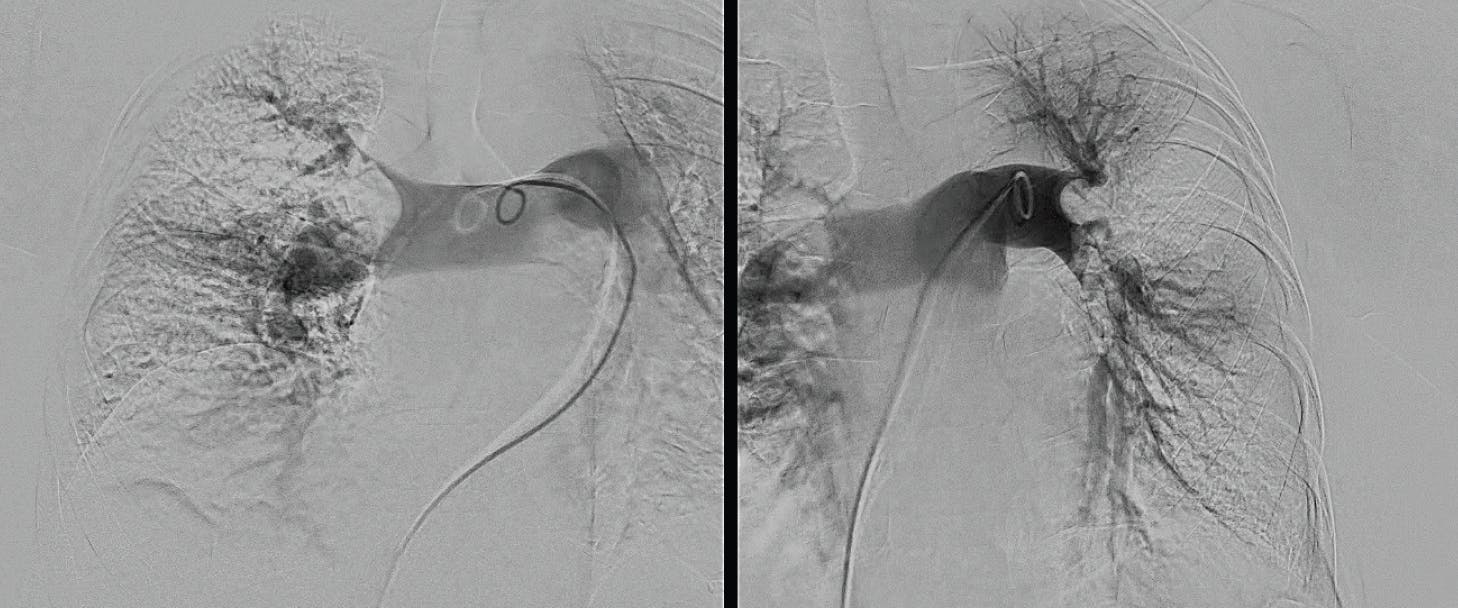

INTERVENTION

Access was obtained in the right groin, and an angiogram was performed to confirm the patency of the inferior vena cava and the iliac veins. Over the wire, a 16-F, 33-cm Gore DrySeal sheath was placed, and a Swan-Ganz PA catheter was advanced to the PA to measure the hemodynamics and measure the cardiac output. After exchanging for the 16-F Lightning Flash aspiration catheter in the right lung, aspiration thrombectomy was initiated (Figure 3).

Figure 3. Intraprocedural angiogram.

Upon confirming vessel patency and thrombus removal with an angiogram (Figure 4, Figure 5, and Figure 6), right heart catheterization from the side port was performed, showing a significant drop in PA pressure from systolic 67 down to 49 mm Hg and excellent hemostasis. By the conclusion of the case, the patient no longer required supplemental oxygen, had no chest pain or shortness of breath, and experienced no significant bleeding. The patient was cleared for discharge the next day.

Figure 4. Post-thrombectomy right lobe angiogram.

Figure 5. Post-thrombectomy left lobe angiogram.